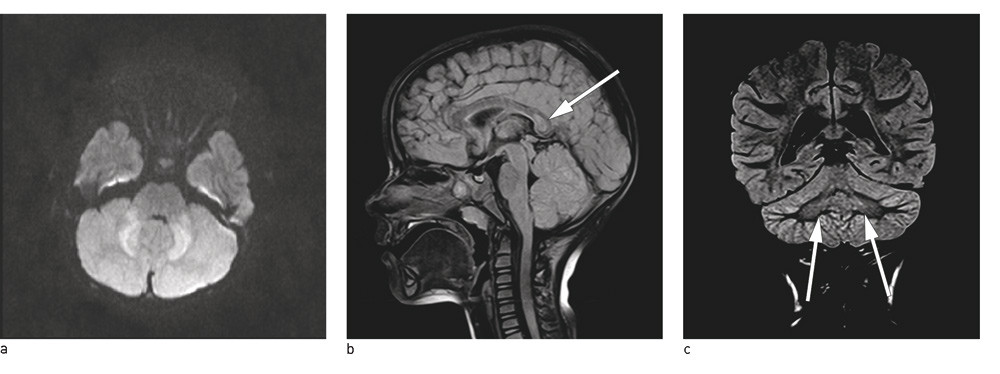

Det ble rekvirert MR cerebri på mistanke om akutt demyeliniserende encefalomyelitt. Denne viste redusert diffusjon i nucleus dentatus bilateralt i cerebellum. Det var også lett signalavvik på T2-vektet sekvens i samme område. Tilsvarende signalavvik og diffusjonsavvik ble sett i splenium corpus callosum. Ingen patologisk kontrastoppladning og intet annet patologisk ble påvist i øvrige deler av hjernen.

I beskrivelsen av MR-undersøkelsen ble heteslag, bruk av metronidazol, virale infeksjoner, blant annet enterovirus, rotavirus og respiratorisk syncytialvirus, diskutert som mulige differensialdiagnoser til bildefunnet (fig 1).

Mutisme (stumhet) er assosiert med forandringer i lillehjernen og ses hos barn etter operative inngrep i bakre skallegrop. Ikke-kirurgisk cerebellær mutisme er sjeldent, men kan ses etter vaskulære hendelser, traume eller inflammasjon (2). Det er holdepunkter for at skade på nucleus dentatus og den dype grå substans i cerebellum bidrar til at mutisme oppstår. Forstyrrelser i den dentotalamokortikale bane spiller også en rolle (2, 3). Vår pasient hadde signalforandringer i nucleus dentatus bilateralt på MR. Dette kunne forklare hennes cerebellære symptomer med uklar tale og etter hvert stumhet før innleggelsen.

Pasienten vår hadde også symptomer på encefalitt med sløvhet. De sammenfallende encefalittsymptomene med signalavvik og diffusjonsavvik i splenium corpus callosum kunne passe med mild encefalopati med reversibel bakre hjernebjelkelesjon (mild encephalopathy with a reversible splenial lesion). Dette er et klinisk og radiologisk syndrom som hos asiatiske barn er beskrevet som en benign tilstand som ikke gir nevrologiske sekveler. Den har vært assosiert med ulike virus, som rotavirus, influensavirus, adenovirus og kusmavirus (3, 4).

Etter MR-funn i cerebellum og splenium og funn av rotavirus i avføringen ble diagnosen rotaviruscerebellitt stilt. I etterkant ble det utført PCR-undersøkelse av spinalvæsken, men rotavirusnukleinsyre ble ikke påvist. Rotavirusantigentest var også negativ.